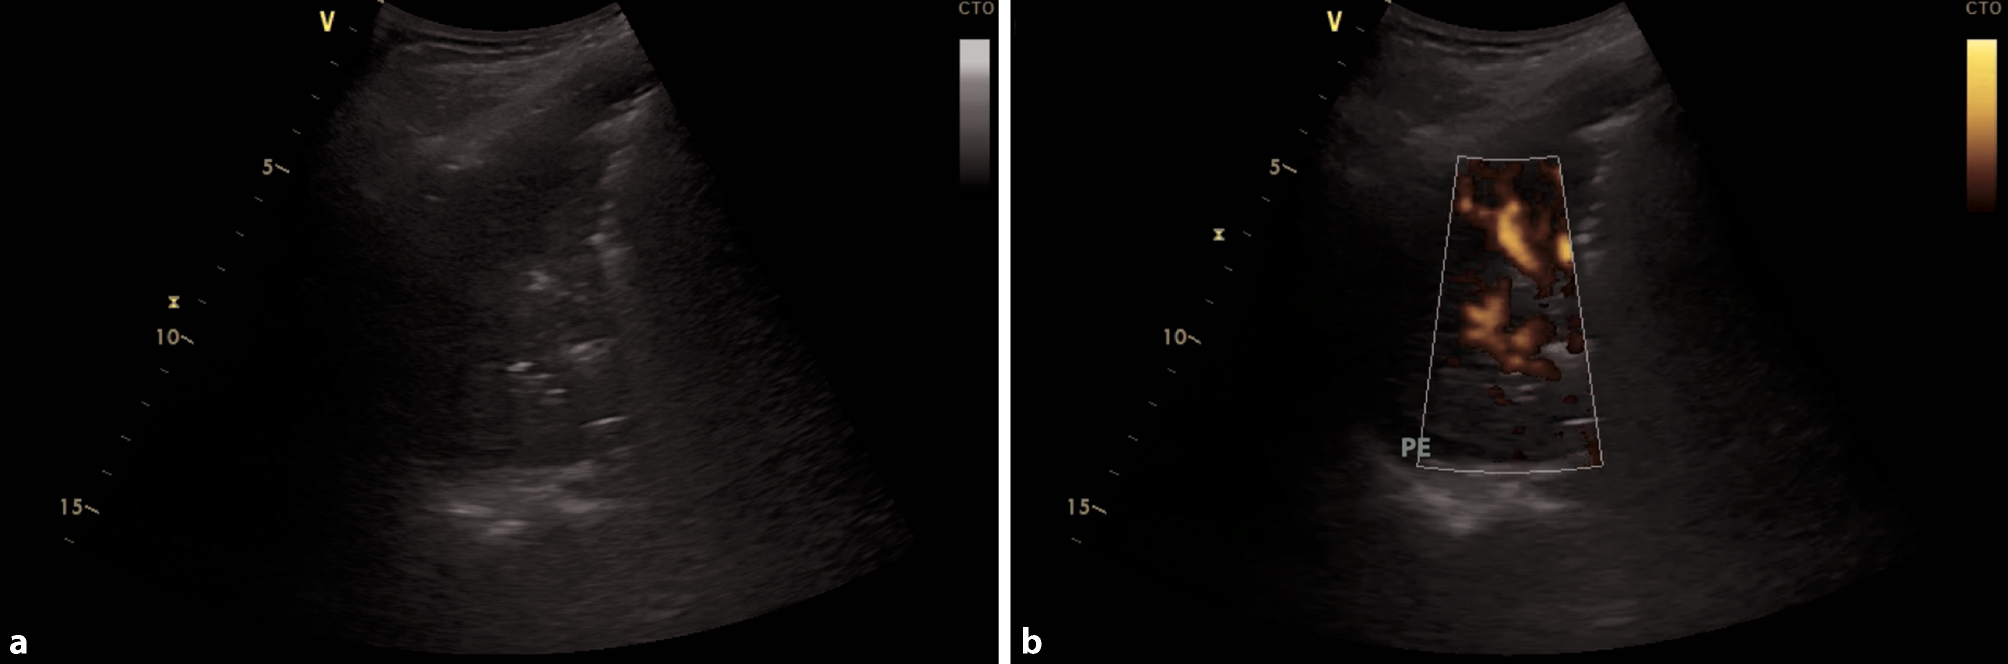

Fig. 3

Bacterial superinfection of the left lower lung lobe in COVID-19. a Large consolidation with air bronchograms in a bacterial superinfection in COVID-19. b Same consolidation with power Doppler to display vascularization, a small pleural effusion is seen (PE)

Dynamic air bronchograms (hyperechoic artifacts moving with the respiratory cycle) are observed within areas of consolidation. Fluid bronchograms (bronchi filled with anechoic fluid within areas of consolidation) present frequently as well. Consolidations can involve entire lobes or whole lungs [24, 35]. Doppler can be used to identify vascularization in consolidations, which is an additional indicator of pneumonia: a tree-like appearance of vessels in color Doppler and a predominately triphasic flow signal in pulsed wave Doppler, can be used to identify pulmonary arteries in consolidations. Monophasic blood flow is found in bronchial arteries. This can be help detect complications such as necrosis, by visualizing hypoechoic areas with no blood flow [36, 37].

Overall, pleural effusions in the context of bacterial superinfections tend to be small and localized in patients with COVID-19 [28]. If large pleural effusions are present, other differential diagnoses, such as heart failure (in particular right ventricular failure), kidney failure, and liver cirrhosis, have to be considered (Fig. 4b; [38]).